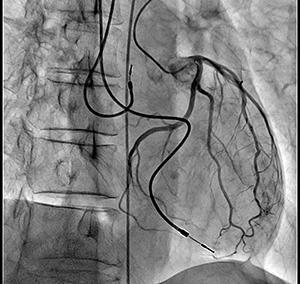

左冠動脈造影画像

※ノイズが少なく明瞭なコントラストで血管が造影される。